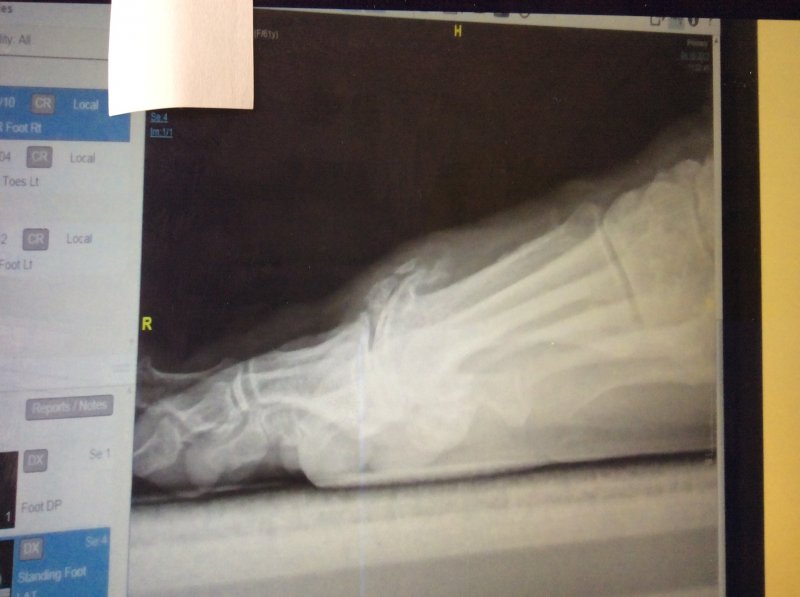

IMG_1360.JPG IMG_1359.JPG This morning we have been down to the hospital to see the results of my right foot X-ray and to have a chat with the consultant about what is going to be done this time.I didn't know it but now can understand why I am in so much pain is that my big toe as well as having a bunion my toe has grown new bone which they call spurs at the Arthritic site in the toe so these will have to be sorted at the same time as they get rid of the bunion.When the Consultant pressed on the spot I nearly went through the roof as it hurt so much:sad:

Have signed the consent forms and have been asked if I have any holidays coming up.Evidently the list is shorter this time but Consultant reckons the waiting time will be a couple of months and at least the surgeon won't have as much work to do on my foot this time round:fingers crossed:

The bit that is sticking up is the bone spur that is causing me all the grief:sad: